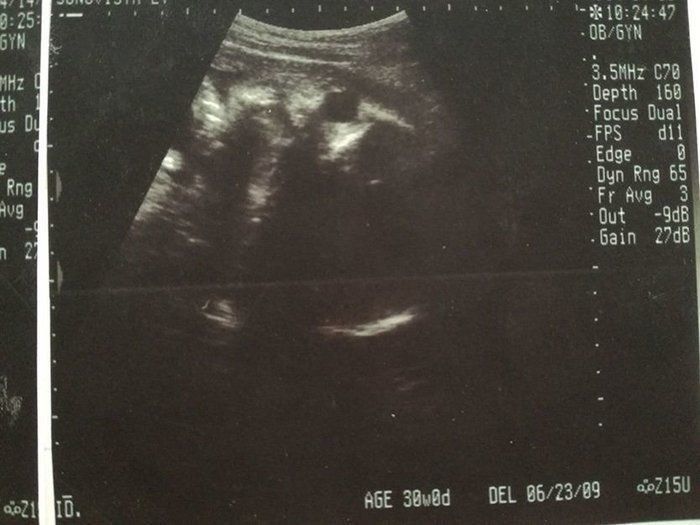

なつさんの妊娠30週目のエコー写真

どんな顔かわかるようになってきました

エコーで顔立ちがはっきり見られるようになりました。チェックしているときにしゃっくりをしていたのも見られました。恒例になっていたおしりチェックをしてもらうと、突然おしりの間に男の子のしるしが! 「今までの検診で何度も見ていたのに、どうして急にわかったんだろう」と家族と驚きました。